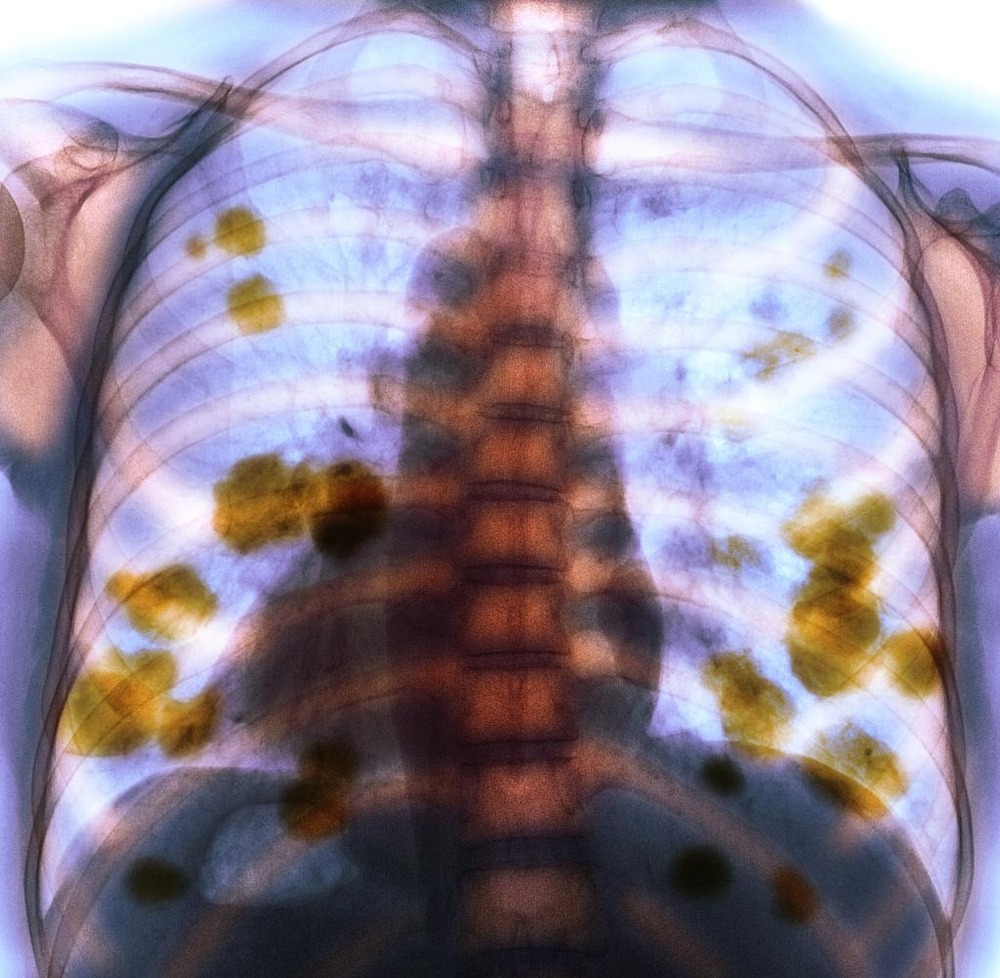

A CT scan can provide a much clearer map of what is happening in the chest, including the size and location of a mass, whether lymph nodes look involved, and whether there are multiple lesions that might suggest spread.1, 7

Because many lung lesions are metastatic, and because primary lung tumours can spread, vets often recommend “staging” tests. This can include blood and urine tests, more detailed chest imaging, and sometimes an abdominal ultrasound to look for a primary tumour elsewhere or signs of spread.1, 7

• Evidence of metastasis (spread)1, 7

On the other hand, when lymph nodes are involved or multiple tumours are present, survival times are often shorter, and the plan may focus more on maintaining comfort and breathing quality rather than cure.7